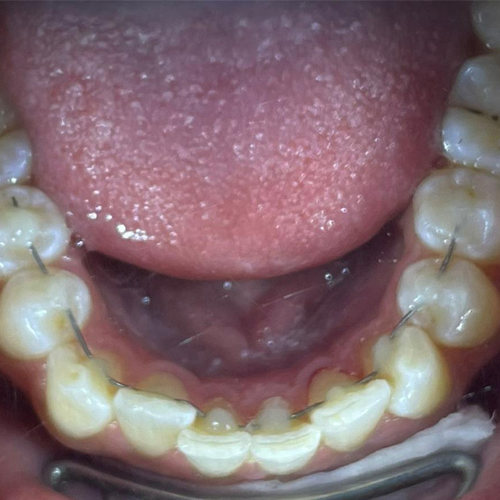

Comprueba en la práctica cómo el conocimiento se transforma en resultados reales a través de los casos de nuestros alumnos.

SALA DE PROCEDIMIENTOS

Siga clases prácticas y la evolución de casos clínicos reales directamente desde la clínica del Dr. Ary Nunes.